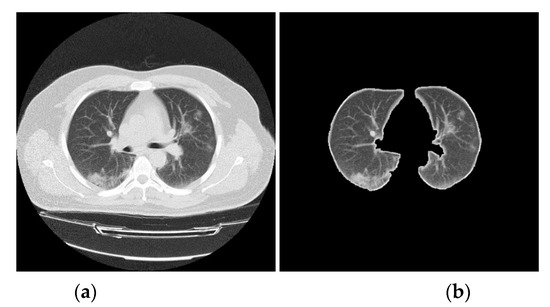

3.2. CT Lung Scan Preprocessing